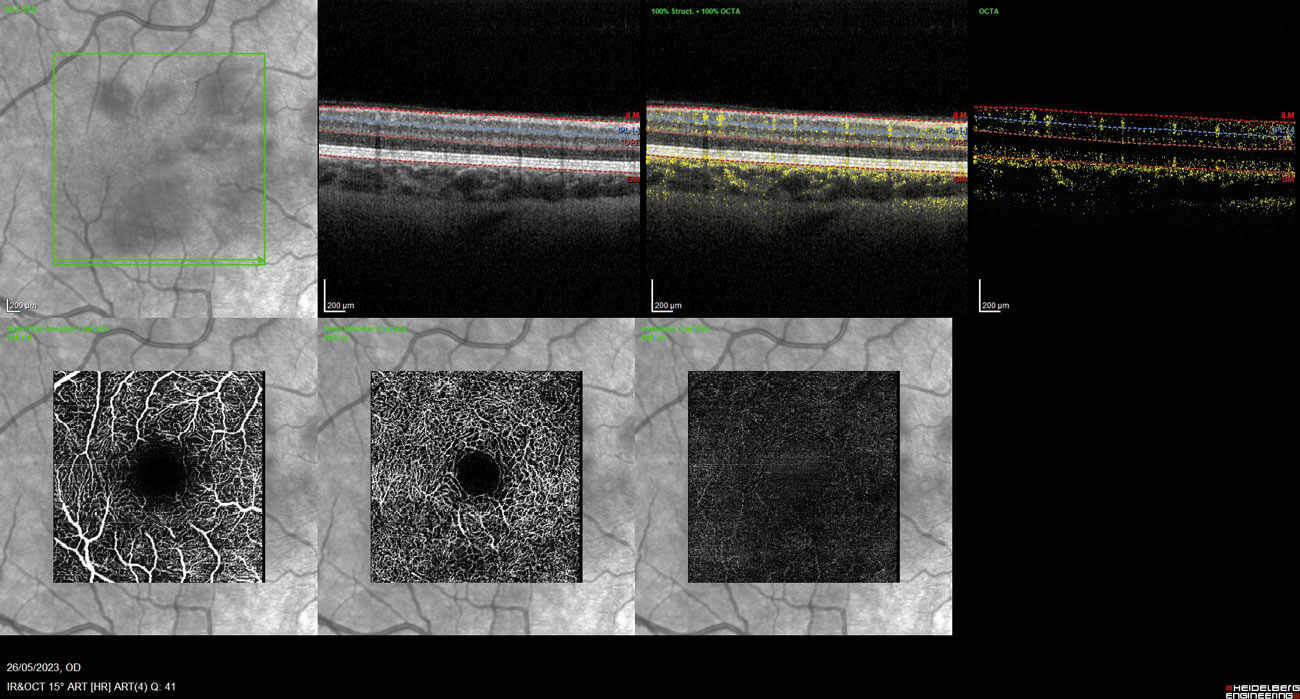

Figures 2a and 2b: OCT angiography left eye (2a - top) and right eye (2b - bottom).

Fundoscopy showed evidence of discrete foveal reflex changes, which on further evaluation with optical coherence tomography (OCT) macular view showed multiple areas of outer retinal disruption (see Figures 1a and 1b). Optical coherence tomography angiography displayed evidence of reduced flow in the deep retinal plexus, consistent with ischaemia (Figures 2a and 2b). These retinal imaging findings correlated with the patient’s subjective visual changes, as noted on their Amsler grid drawings (see Figures 3a and 3b).